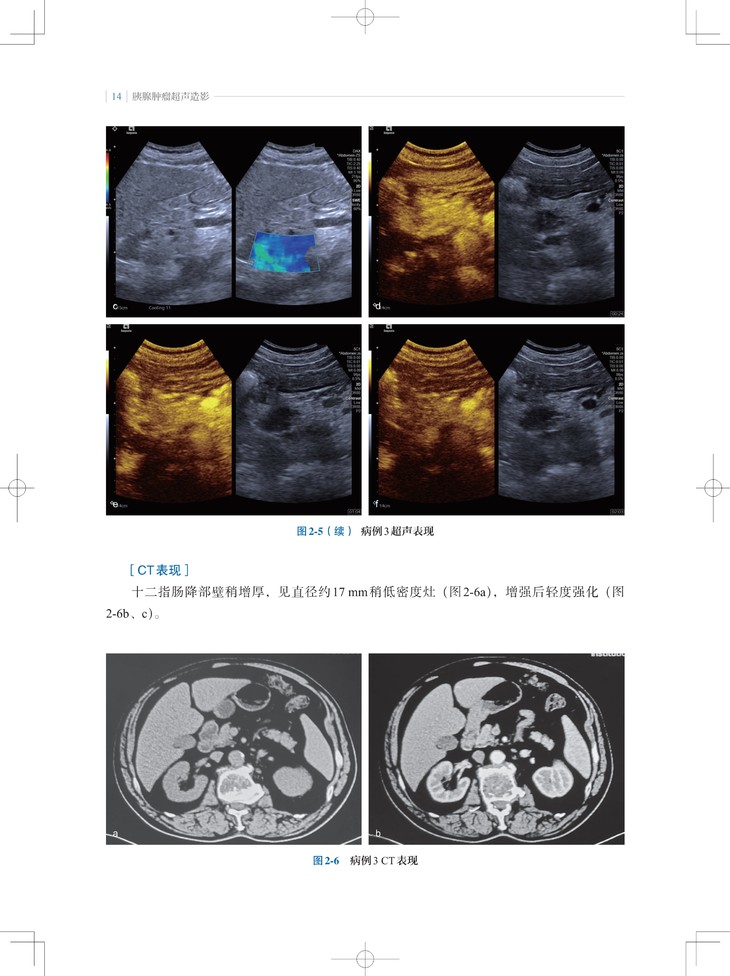

本书是“东方超声文库”系列之一,介绍了超声造影剂和实时超声造影技术在胰腺肿瘤诊疗领域的最新应用。内容包括胰腺肿瘤的超声造影表现特点、诊断要点,超声造影在随访胰腺癌非手术治疗、预测胰腺切除术后并发胰瘘、胰腺癌微创介入治疗中的应用;此外,通过与胰腺肿瘤的CT、MRI等影像学表现的对比,让读者对超声造影检查技术有更全面的认识。

2. 内容实用:超声造影不但提高了胰腺肿瘤定性诊断的准确性,而且能反映胰腺肿瘤微血管的血流动力学改变,本书对从事胰腺肿瘤诊断和治疗的各领域、各级临床医师有实用指导意义。

3. 编写方式契合临床:不仅有胰腺肿瘤造影影像图,还有与CT/MRI等影像学表现的对比及手术照片。